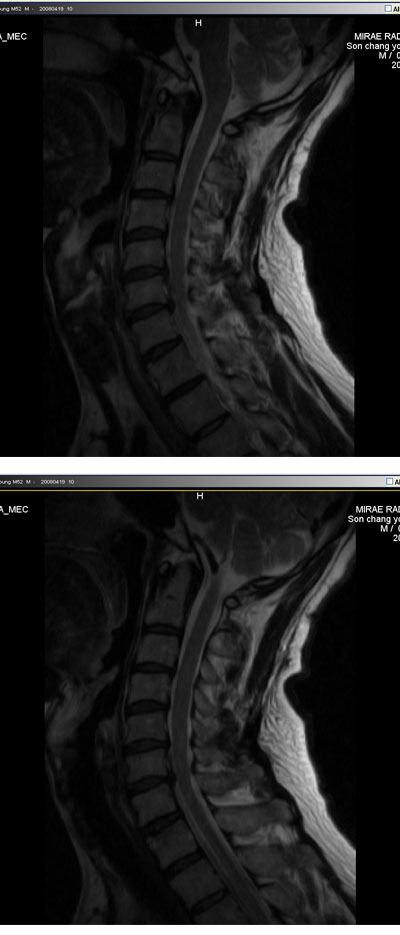

â* ũ ŷе mri (ֹȣ : 4ee6c7e9f04b ) ϼ е6 ߰ ͻ þȳ ŷе 0711 () ũ, 1C.ڵ, 1C., 1C.̸ , 1C.ڵӸ , 1C.ھ, 1C.ٱ (), 1C.߷ (), 1C.Ƿ (), 1C.ڱ ֺ , 4C.û°, 4C.5C.ھ, հ ̳ , 6C.ڸ , 6C. κ Ḳ , 6C.ھ Ḳ , 6C.ڻ , 6C.7C.ھ հ ̳ 7C.ڿʰ , 1T.ڼյ չٴ , 1T.ڼո , 1T.ڼհ ü ̳ , 1T. κ , 3T.ڵ , 2T. Ʒκ 4T. ȯ, 6T., 6T. Ű , 6T.ټ , 6T.ٽƮ 6T.ڼȭҷ 10T.ٸǷ, 4L.ڿ, 5L.ڹ߸̳ , 5L.ڹ ٸ ȯ, (). ڱô ũ(߰Ż), ũ(߰Ż)ġ, հ , , հ , ġ, , Ḳ , , Ḳ ġ Ǵ , , 㸮ũ(߰Ż) ߿ ġ , 㸮 ̳ ġ ߷, , нɷ , dz, , Ǵ ġ Ǻι̿, Ǻγȭ ָ, ָ, ָ Ǵ ġ ȭҷ ġ ͳ õ ͳ ˻ڷ õ |